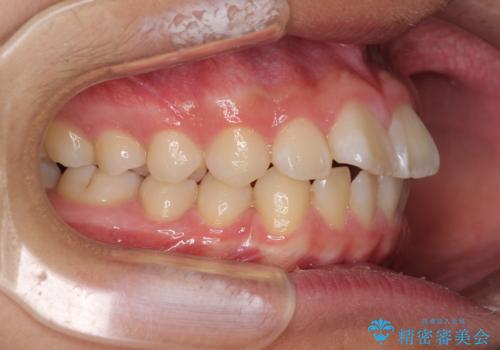

- 上下前歯のデコボコを改善したいとのことで来院された患者様です。

中学生と言うこともあり、1年強の短期間で終了しました。

歯磨きがしっかりとできないと虫歯になるリスクがありましたが、治療期間中は清潔な状態を保っていただけました。